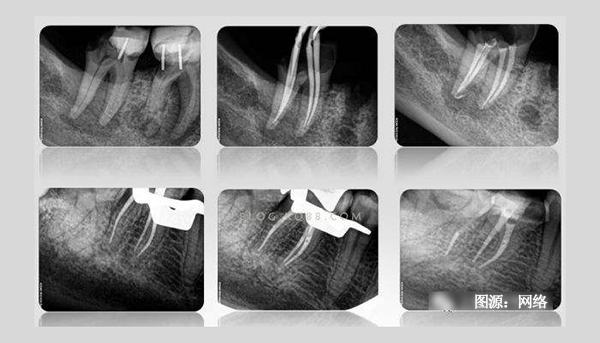

根管治療時為什么需要反復(fù)拍攝X光片?

有根管治療史的患者都知道,在根管治療過程中需要反復(fù)拍攝多次X光片。一般說來,完成一顆牙的根管治療至少需要3張X光片:術(shù)前X光片、術(shù)中X光片、術(shù)后X光片。

術(shù)前X線片反映患牙及牙周組織的客觀情況—根管長度、根尖周牙槽骨密度等,目的主要是幫助牙醫(yī)了解患牙的病變范圍、牙根情況、根管數(shù)目以及根尖周病變情況,根管是否存在鈣化,幫助醫(yī)生判斷患牙的預(yù)后以及根管治療的難度,是牙科治療的依據(jù)。

術(shù)中需要對根管預(yù)備情況進(jìn)行檢查,主要是輔助測量根管長度,看根管預(yù)備是否到位,牙齒里面的神經(jīng)是否清理干凈。對于難度較大者需要一邊進(jìn)行根管預(yù)備一邊插針拍X線片,以監(jiān)測根管預(yù)備的方向和程度以求良好的治療效果。

術(shù)后X線片是為了觀察根管治療是否徹底,根管內(nèi)充填物是否合適,判斷根管治療充填的質(zhì)量是否到位。術(shù)后拍攝X線片,有助于醫(yī)生對治療效果的判斷,如果治療結(jié)果不滿意可及時更正,以免出現(xiàn)不必要的復(fù)診。根管治療術(shù)后拍X線片片已成為檢驗根管治療質(zhì)量的手段之一,是根管治療規(guī)范化操作的一部分。